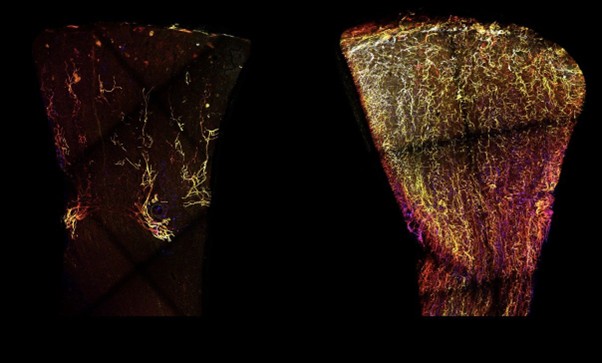

Jaffree and colleagues published works recently, combining single cell RNA sequencing with powerful 3D imaging to “map” lymphatic vessels in donor kidney tissue, demonstrating changes in lymphatic vessel ‘mapping’ during chronic rejection (Figure 6; 36).

Figure 5. The lymphatic vessels of a healthy kidney (left) are represented in yellow, compared to kidney undergoing rejection (right). Jaffrey et al (2025) [Image from https://tinyurl.com/aenuws5n accessed 03/10/25]